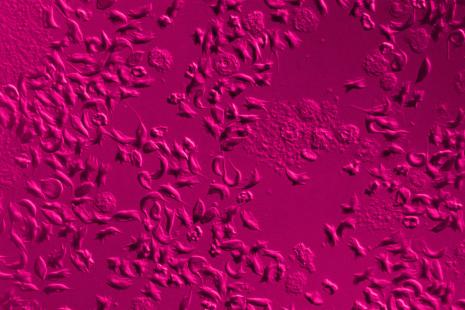

Une des études publiées le 11 juillet propose une estimation de la prévalence mondiale de la drépanocytose et du poids de la mortalité de 2000 à 2021. Sur la période, les taux d'incidence nationaux étaient « relativement stables », mais le nombre total de naissances de bébés atteints de drépanocytose a augmenté globalement de 13,7 %, pour atteindre 515 000 cas, « principalement en raison de la croissance démographique dans les Caraïbes et en Afrique subsaharienne occidentale et centrale », est-il souligné.

Dans le monde, la population vivant avec la drépanocytose a augmenté de 41,4 %, passant de 5,46 millions en 2000 à 7,74 millions en 2021. Et, 376 000 décès liés à la drépanocytose ont été enregistrés dans le monde en 2021, dont 81 000 chez des enfants de moins de cinq ans.